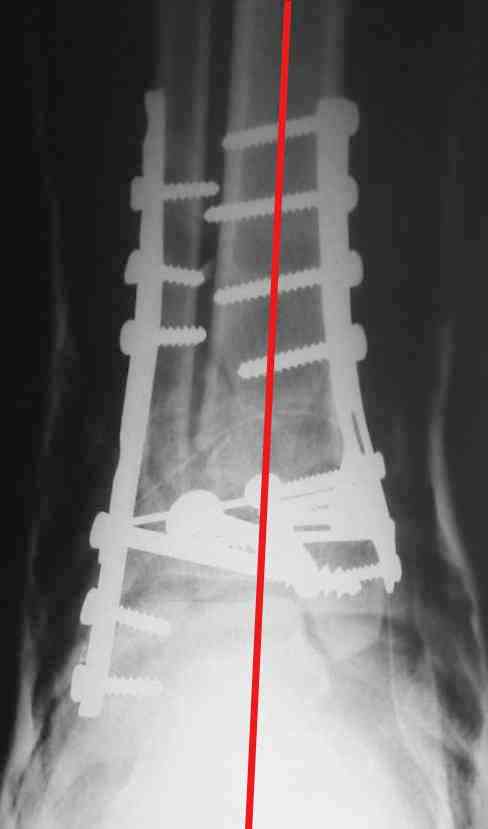

На представленном снимке видно, что эпифиз смещен латерально.

Однозначно сказать сложно.Расстояние между тараном и медиальной лодыжкой меньше чем между тараном и крышей большеберцовой кости.Это может быть за счёт не правильной укладки.Пока не отчаиваетесь.Главное вы поняли принцип.Сделайте несколько проекций прямых и посмотрим.Для всех интересно.С уважением

В голеностопном суставе обязательны 3 стандартные ренгенологические проекции: прямая, латеральная и мортиз. Без них невозможно трактовать состояние голеностопа.